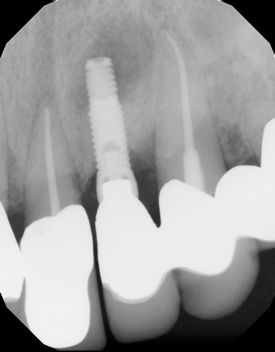

In this case, a dental implant that had been placed 10 years prior was functional, stable, and esthetically acceptable to the patient. However, a significant fistula was present on the facial-apical aspect of the ridge in the maxillary lateral incisor area. This area was painfully sensitive to touch and demonstrated purulence when squeezed. To evaluate the lesion, first, a conventional digital radiograph was acquired, which revealed an apical radiolucency at the apex of the implant (Figure 1). Further analysis using cone-beam computed tomography (CBCT) demonstrated a fistula from that site to the oral environment (Figure 2). Treatment options were discussed, including removal of the implant, followed by grafting, a healing period, and replacement of the implant and implant-retained crown. If this option was selected, a transitional appliance would need to be created. Another option was to attempt to salvage the implant and implant crown by treating the infection and grafting the site to create a new boney wall and eliminate the fistula. Ultimately, the patient accepted this option to attempt to salvage the fixture and crown.

(1.) Preoperative radiographic evaluation demonstrating a large radiolucency at the apical third of the body of an implant fixture replacing the patient’s maxillary left lateral incisor. The implant was stable, and the prosthesis was deemed esthetically acceptable by the patient.

Figure 1